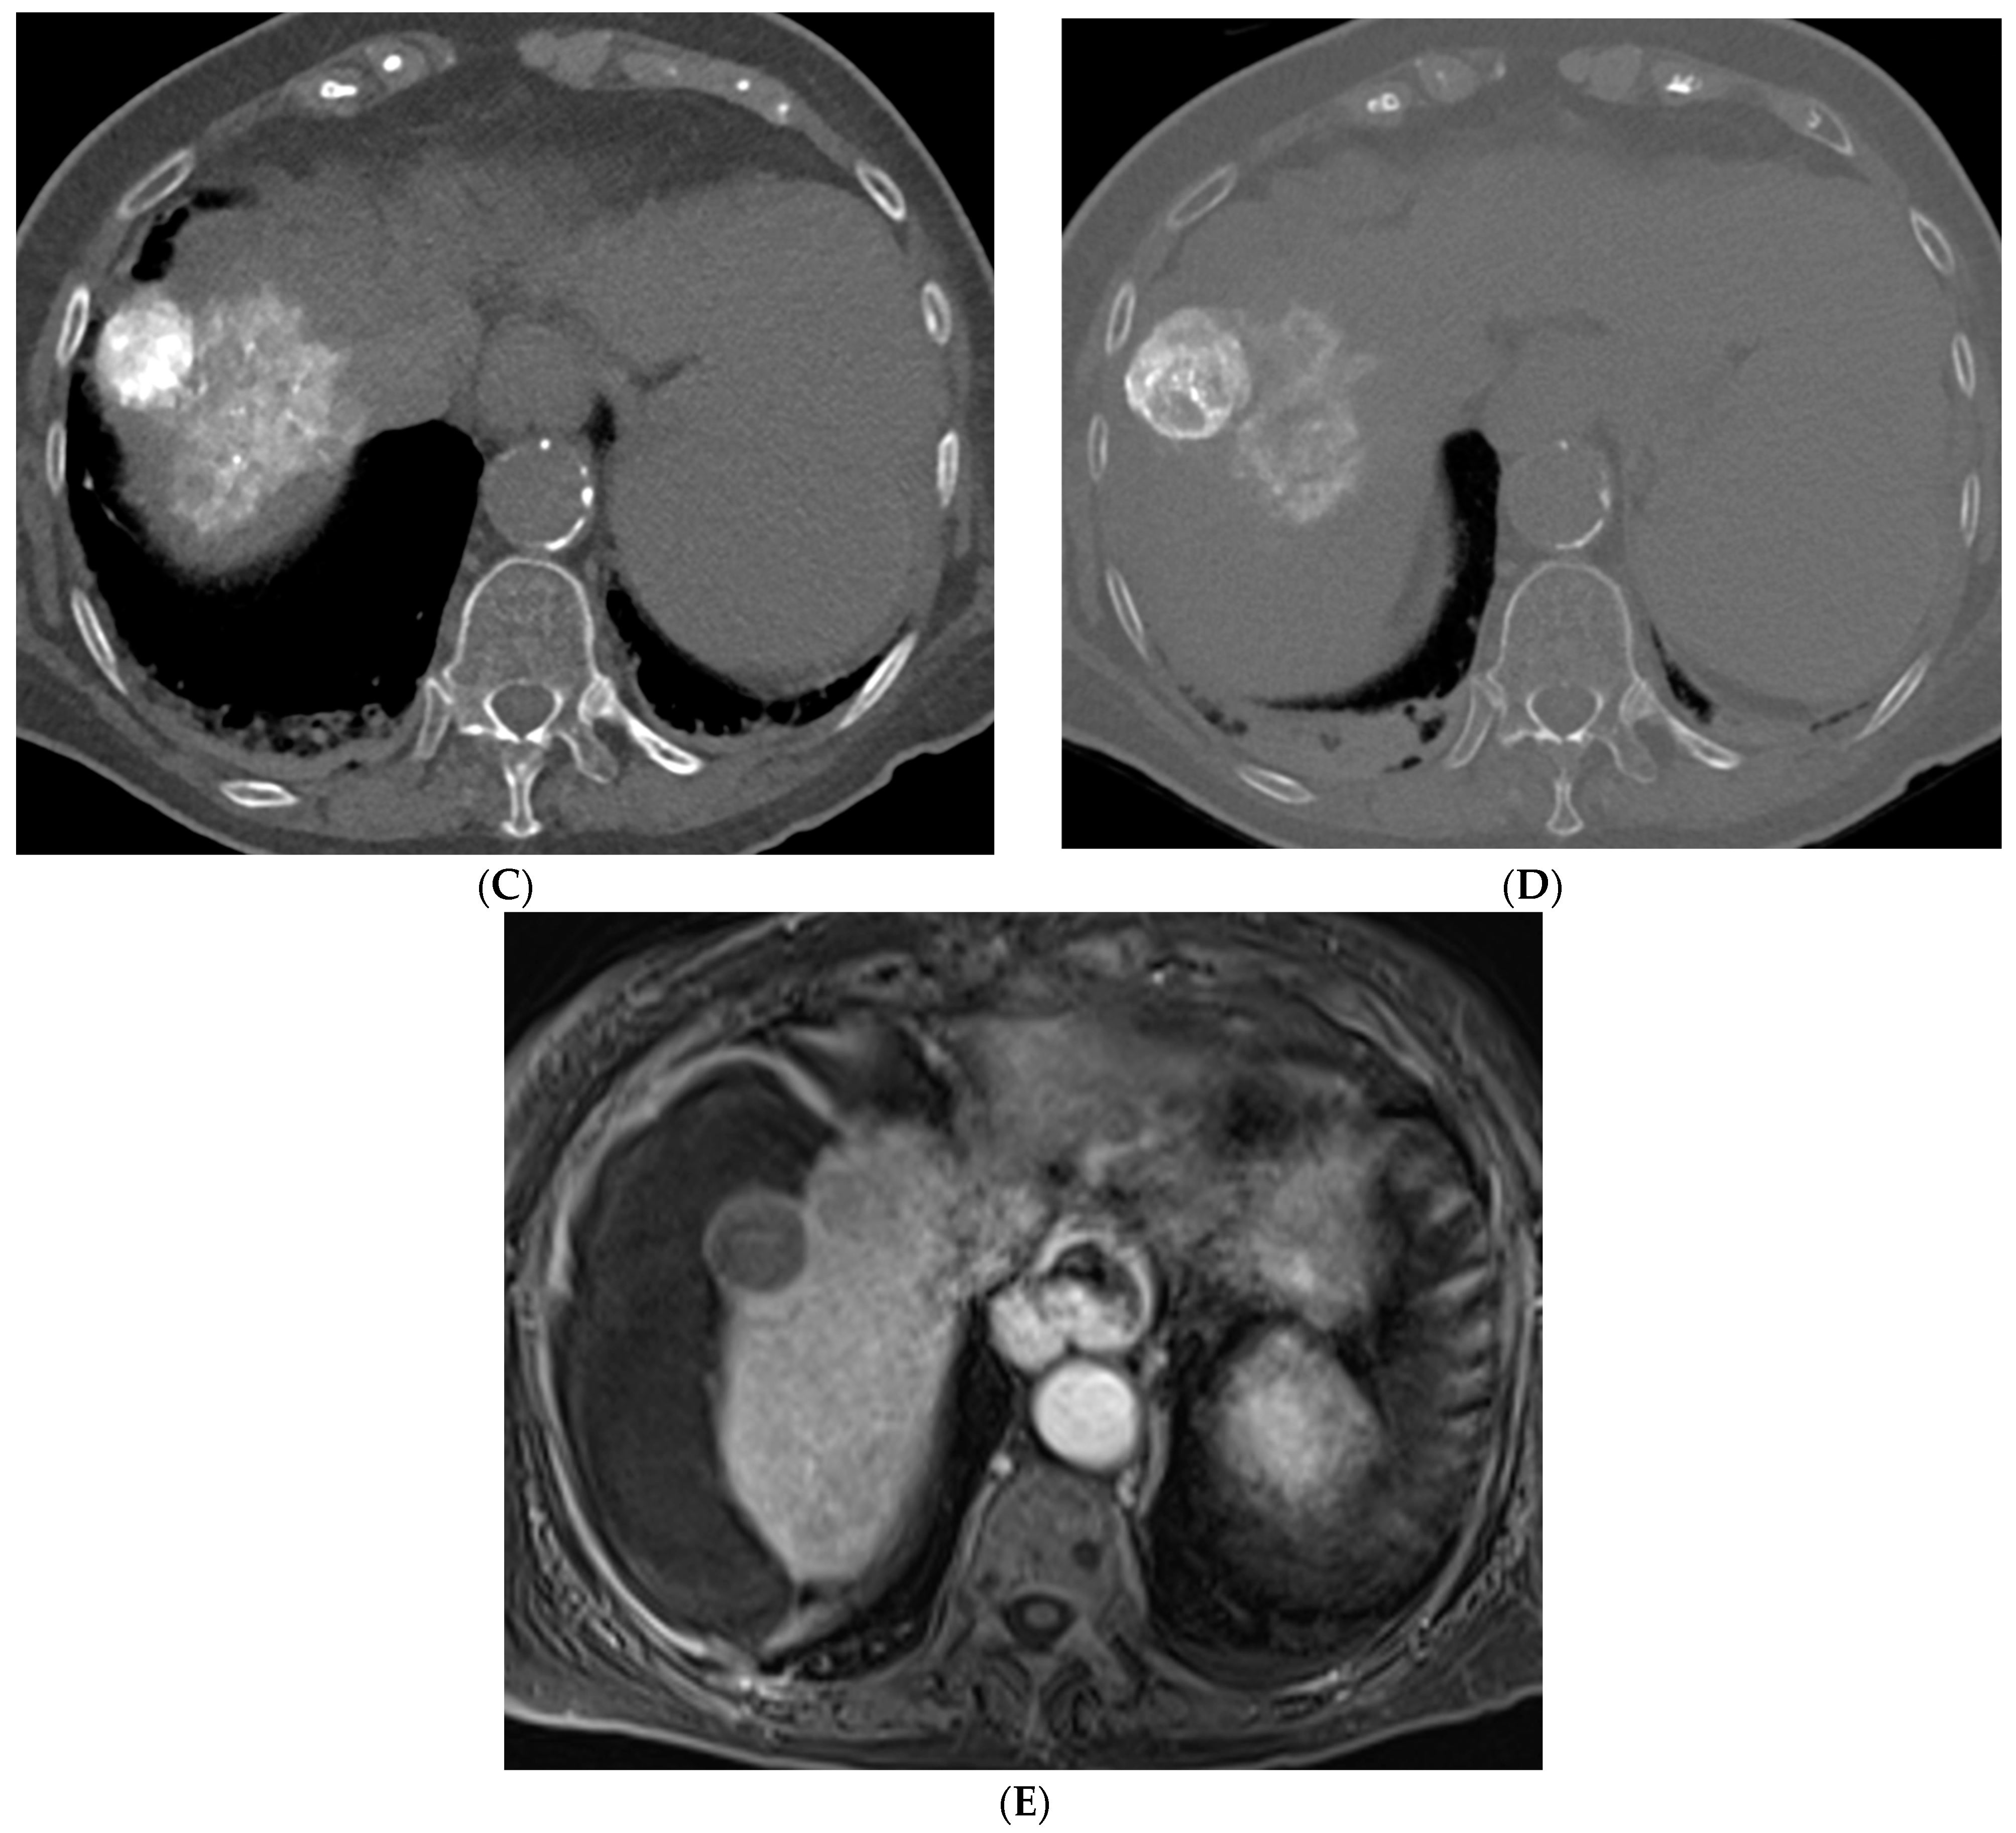

Figure 3. 73-year-old man with non-cirrhotic HCC treated with 90Y radiation segmentectomy. (A) Arterial phase MRI showing a 4 cm arterially enhancing lesion in hepatic segment 5. (B) Delayed phase MRI showing washout of the lesion. (C) Intraprocedural CTA demonstrating supply to the posterior aspect of the mass from one of the segment 5 branch arteries. (D) Intraprocedural CTA demonstrating supply to the anterior aspect of the mass from a separate segment 5 branch artery. The Y90 dose was delivered as a split dose between these two arteries. (E) Follow up arterial phase MRI 3 months after treatment demonstrates wedge-shaped post-treatment changes in hepatic segment 5 with expected parenchymal enhancement and capsular retraction with no residual enhancement of the targeted tumor. (F) Follow up delayed phase MRI demonstrates no wash-out of the enhancing parenchyma to suggest residual viable tumor, consistent with complete response.

TARE was originally offered as an alternative to TACE in patients with portal vein thrombosis (PVT), a common complication of HCC [10,32]. This is based on the principle that TARE is non-embolic and thus can be used safely in cases of PVT and does not preclude future treatment with TACE [10]. TARE involves the radioisotope Yttrium-90 (90Y) which undergoes beta decay and has a tissue penetration of 2.5 to 11 mm [9]. In the LEGACY trial, patients with unresectable HCC who underwent TARE demonstrated an objective response rate of 88.3% with a 3-year overall survival of 86.6% [33]. Other studies have focused on comparing the efficacy and outcomes of TACE versus TARE in early and intermediate stage HCC [34]. In the PREMIER trial, patients who underwent TARE had significantly longer time to progression (TTP) (>26 months) versus patients who underwent TACE (8.2 months; p = 0.0012) with similar median survival time [34]. In the TRACE II trial, patients with intermediate stage HCC were randomized to either TARE or DEB-TACE [35]. The primary endpoint of time to tumor progression was significantly longer in the TARE versus DEB-TACE group (17.1 versus 9.5 months; p = 0.002). Median overall survival was also significantly longer in the TARE group (30.2 versus 15.6 months, p = 0.006). Both groups had similar rates of adverse events and 30-day mortality [35]. Other studies have shown better tolerated side effects, decreased length of hospital stays, and fewer treatment sessions required with TARE [36,37].

Variations in TARE include radiation segmentectomy and lobectomy [10]. In patients in which resection or ablation is not feasible, radiation segmentectomy can offer an ablative level treatment dose to lesions confined to less than two segments while sparing the remaining normal liver parenchyma [10] (Figure 3). The RASER trial demonstrated that radiation segmentectomy in patients with a solitary HCC tumor in an unfavorable location for ablation resulted in high rates of complete response (24/29 patients, 83%) with low rates of adverse events [38]. In the DOSISPHERE-01 study, patients with unresectable HCC were randomized to either standard dosimetry (120 ± 20 Gy) to the diseased lobe or personalized dosimetry (>205 Gy) to the index lesion. Patients in the personalized dosimetry group had significantly higher rates of objective response to therapy with similar rates of adverse effects [39]. Radiation lobectomy is yet another application of 90Y that involves administering a higher dose to the diseased lobe of the liver, with the goal of inducing tumor death and atrophy of the diseased lobe with resultant compensatory hypertrophy of the normal lobe. This concept can allow patients who would not otherwise be candidates for surgical resection due to a small future liver remnant (FLR) to be able to undergo resection [10].

Figure 4. 72-year-old man with HCV cirrhosis and HCC treated with combined cTACE and cryoablation as a bridge to transplant. (A) Arterial phase MRI demonstrates a 2.2 cm segment 4a hypervascular lesion. (B) Digital subtraction angiography images during cTACE procedure demonstrate that the tumor was supplied by both the segment 4a branch vessel (image shown) and segment 2 artery (not shown). cTACE was performed using doxorubicin 50 mg, cisplatin 100 mg, and mitomycin 10 mg followed by PVA 150–250 micron particles. (C) A non-contrast CT scan performed on post-operative day 1 demonstrates a heterogeneous uptake of ethiodized oil within the tumor. Cryoablation was then performed using two probes. Coronal and axial CT images from the procedure demonstrate the probes adjacent to the ethiodized oil staining (D) and the ice ball (E). (F) A follow up contrast enhanced MRI in the arterial phase demonstrates no residual viable tumor.